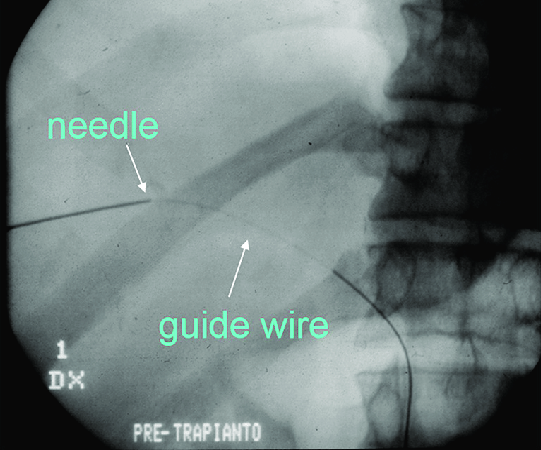

الاجراءات تبدأ دائما بـ(Seldinger Technique)

في بداية كل فحص يبحث الدكتور عن المنطقة المناسبة للدخول من خلال الوريد أو الشريان وكل فحص له بروتوكول في تحديد مكان الدخول (Vessel Access) فبواسطة جهاز الالتراساوند يبحث الدكتور عن مكان الدخول المناسب ثم إذا حدده يخدر المريض موضعيا...

ثم يدخل الابرة بالشريان أو الوريد ويتأكد من ذلك من خلال متابعة الابرة في الالتراساوند ويتأكد أكثر انه داخل الوريد إذا خرجت قطرات دم من الابرة، ويتأكد انه شريان إذا تناثر الدم بشكل سريع بسبب أن ضغط الدم أكبر في الشريان من الوريد.

نعيد من جديد..

إذا حدد الدكتور المكان المناسب (Vessel Access) يخدر المريض موضعيا (Local)،ثم يدخل الابرة (Puncture Needle) من خلال الوعاء الدموي،ثم يدخل بعد ذلك الـGuide Wire، ثم يخرج الابرة ويدخل الشيث ليحفظ الاكسيس، ومن ثم الخطوات التالية تعتمد على نوع الفحص أو الاجراء المعمول.

هذه بإختصار خطوات (Seldinger Technique) الذي يعتبر أساس أي اجراء يتم في قسم الانجيو.

*الخطوة الرابعة بالصورة المرفقة لم اذكرها بالشرح بالتغريدة السابقة.. وهي بعد ما يخرج الدكتور الابرة يوسع بالمشرط الاكسيس حتى يدخل الشيث بشكل اسهل.